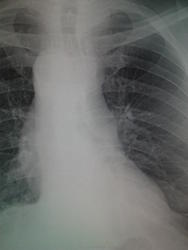

Бок, если верно поставлен, выполнен правый. Аорту праволежащую он выявить помог нам. Но тень, наводящую сомнение на Наталью Ивановну не проявил. И Ленивец отъявленный, верно, про левый бок говорила.) В общем, тень осталась для части коллег не объяснима.)

Она трахею влево оттесняет, значит сама справа находится. Нет неясности.

Бок сначала покажите.

ХитрО!)) Дугу ощущаем и видим, а это уже вопрос другой - без бока не проходим.)

досняли боком